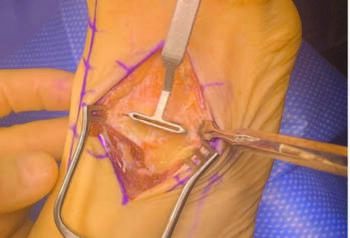

As with metatarsus adductus correction in general, triplanar correction of the first ray depends on a normal second ray position. We must first reveal the true intermetatarsal angle through lesser TMT deformity correction14 to achieve this goal. The essential tenets of this approach are: plane, cut, compress and fixate. The surgeon first makes a six-to-eight cm, longitudinal incision over the third TMT. Oblique fluoroscopy identifes the level of the joint with a metal marker. One should take care to maintain a four cm skin bridge between the dorsomedial and dorsolateral incisions when dissecting the first and lesser TMT sites. Retracting the extensor digitorum longus tendons exposes the brevis muscle which one then dissects and retracts. The surgeon may transect the extensor digitorum brevis tendon slip to the hallux, allowing retraction of the entire muscle laterally as one unit. The surgeon should maintain the superficial peroneal nerve and dorsalis pedis artery in the soft tissue flap between the dorsal incisions.

The keystone nature of the midfoot anatomy at the second and third TMT articulations creates a significant ‘stair-step’ offset, which requires planing to accept the lesser TMT cutting guide in this technique. The surgeon resects the superior joint apices with a planing guide to revise joint anatomy to accept the keel of the lesser TMT cut guide. Release of the soft tissue interval between the third and fourth metatarsal bases will help facilitate deformity correction and fusion surface apposition following the bone cuts. One should maintain LisFranc’s ligament and the plantar cuneometatarsal ligaments as additional tethering points to further stabilize the arthrodesis following hardware application.